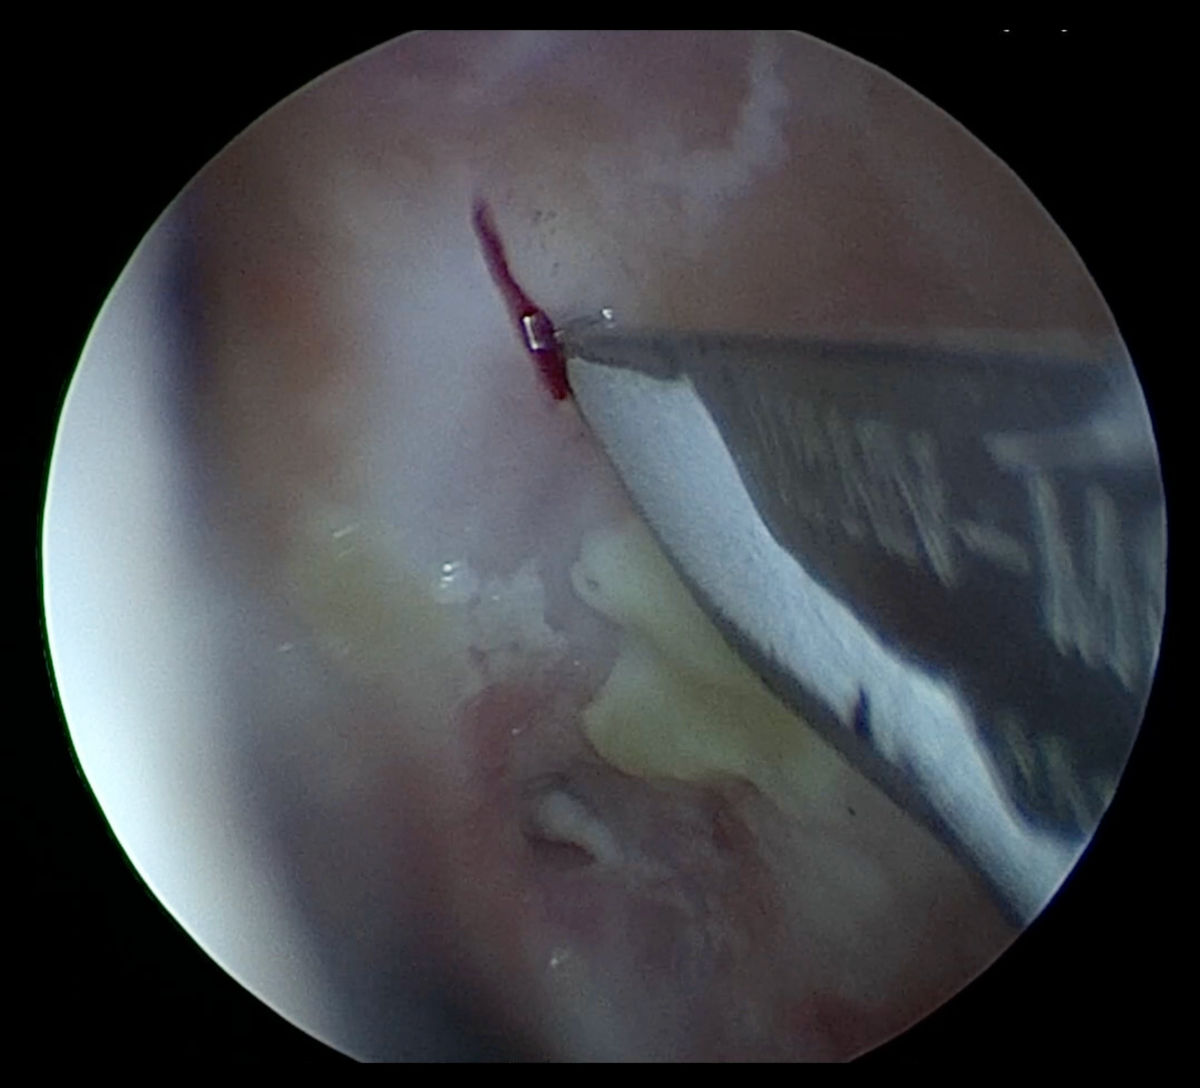

A 4 mm coronary balloon catheter (Boston Scientific, USA) was used to conduct a balloon dacryoplasty on the patient's left side (Fig. 10). An incision was made in the scar tissue developed after the previous DCR surgery (Fig. 11). The balloon catheter was introduced into the nasal cavity through the lacrimal canaliculus, lacrimal sac and the incised scar tissue. The catheter was inflated to 8 atm for 90 seconds, then it was deflated and removed (Fig. 12-13). After debriding the neo-ostium's periphery scar tissues, Mitomycin-C was applied. A significant internal common opening was visible in the immediate postoperative period. The ostium was big, anatomically correct, and functionally patent at the 3-month follow-up. At six months of follow-up, the patient was symptom-free and still receiving immunosuppressive treatment (Fig. 14-15).

Figure 11. Endoscopy view of the left nasal cavity: incision being made in the scar tissue developed after previous DCR surgery.